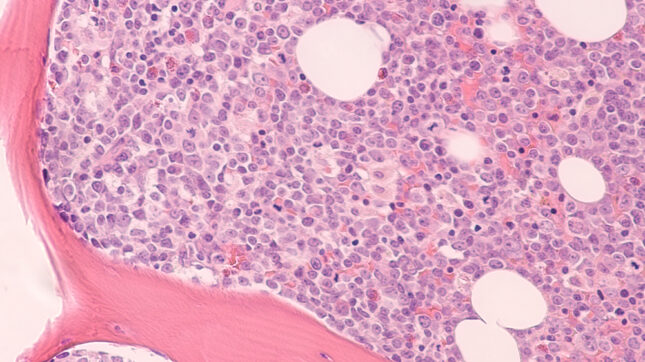

למרות הצלחתן של תרופות חדשות הגורמות למוות של תאי דם סרטניים בחולים עם לוקמיה מיאלואידית חריפה, תאי הלוקמיה מאמצים לעתים קרובות תכונות המאפשרות להם לחמוק מהשפעות התרופות בתוך שנה. כעת, מחקר חדש שהשתמש בדגימות מרקמות אנושיות ובמודלים של עכברים מצא כי עמידותם של תאי לוקמיה לתרופה נפוצה בשם ״ונטוקלקס״ מתרחשת בגלל עלייה מהירה בפירוק ותחלופה של מיטוכונדריה, מבנים בתוך התא המפיקים אנרגיה לשימוש התא. בנוסף לתפקידם בייצור אנרגיה, המיטוכונדריה גם גורם לתאים למות בתנאים מסוימים.

תהליך זה של "מוות תאי מתוכנת" משתבש לעתים קרובות בסרטן. מיטוכונדריה פגומים יכולים גם לגרום ל"אכילה עצמית", המכונה ״מיטופגיה״, שמונעת מהם לשלוח "אותות מוות". המחקר, שנערך בהובלת מדענים מאוניברסיטת ניו יורק ומרכז פרלמוטר לסרטן, הראה כי מיטופגיה מסייעת לתאי לוקמיה להתחמק מההשפעות ההורגות של תרופת הונטוקלקס.

בפרסום בכתב העת Cancer Discovery באינטרנט ב-24 באפריל, החוקרים מצאו כי מספר גנים הקשורים למיטופגיה ב-20 דגימות של חולי לוקמיה בהשוואה לקבוצת ביקורת רגילה. רמתם של גנים אלה הייתה גבוהה עוד יותר בדגימות מחולי לוקמיה עם עמידות לתרופות, לעומת חולים לוקמיה שלא היו עמידים. בולט במיוחד היה הביטוי המוגבר של הגן Mitofusin-2י(MFN2), המקודד חלבון מפתח בקרום המיטוכונדריאלי החיצוני.

ניסויים נוספים בעכברים שבהם הושתל מח עצם מחולי לוקמיה מיאלואידית חריפה הראו כי התרופה כלורוקין, מעכב מיטופגיה ידוע, שיקמה את יכולתו של ונטוקלקס להרוג את התאים הסרטניים.